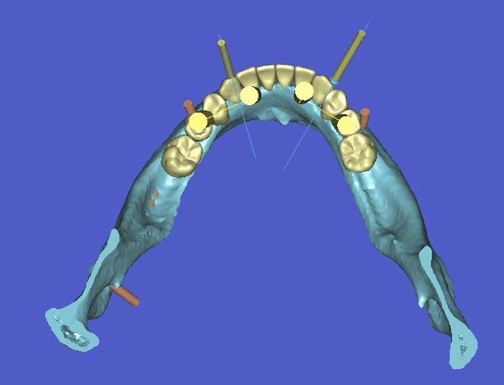

l’informatique au service de l’implantologie

La société Materialise a développé un logiciel SIMPLANT qui permet de simuler la position des futurs implants et de les transférer en bouche à l’aide d’un guide chirurgical.